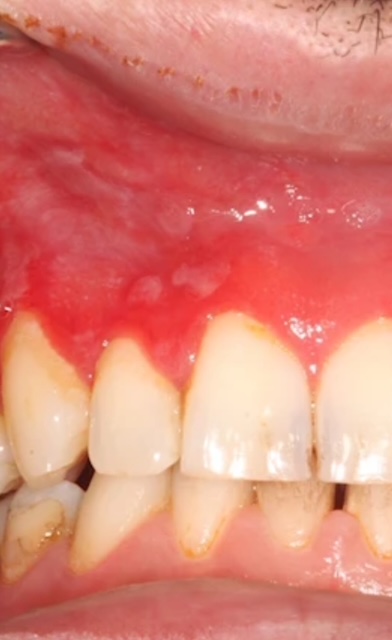

Vid användning av brunt snus blir slemhinnan oftast veckad och får en vit förtjockning där prillan läggs in. En del användare av vitt snus har i stället smärtsamma och tydligt rödfärgade förändringar i tandköttet. Hos vissa uppstår även sår där det vita snuset läggs mot slemhinnan.

– Vi är mer oroliga för de här förändringarna. De ser helt annorlunda ut, med rodnad och uttunnad slemhinna. Vävnadsprover har visat på kraftig inflammation och vi rekommenderar omedelbart snus stopp när man har besvär eller ser förändringar, säger Gita Gale, disputerad specialisttandläkare och en av forskarna bakom studien.

Förändringarna vid användning av vitt snus tycks också vara mer svårläkta. Hos användare av brunt snus återställs tandköttet oftast på några veckor efter ett snus stopp. Skadorna efter vitt snus har visat sig kunna bestå i många månader, till och med uppemot något år.